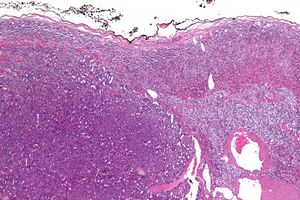

| صورة مجهرية لسرطان قشر الكظر (يسار الصورة - أزرق غامق) والقشرة الكظرية التي نشأت منها (أعلى يمين الصورة - وردي / أزرق فاتح). يوجد لب الغدة الكظرية الحميد (منتصف يمين الصورة - رمادي / أزرق). صبغة هيماتوكسيلين ويوزين. | |